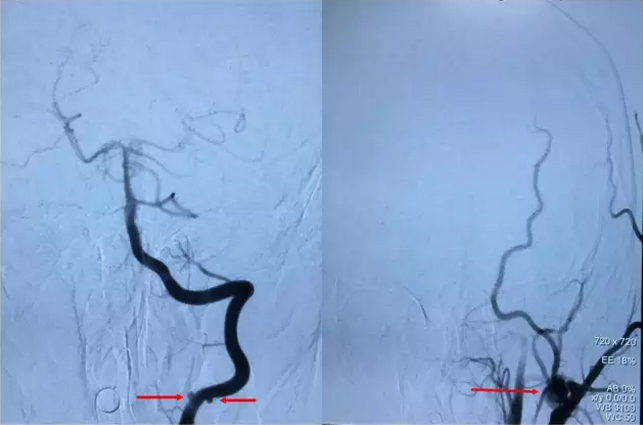

寿记新教授认为,该患儿动脉瘤多发不适宜行传统开刀手术,更适合于血管内介入治疗。于是在认真分析脑血管造影结果后制定了详细而缜密的治疗计划:右侧椎动脉动脉瘤行支架辅助动脉瘤栓塞,左侧颈内动脉海绵窦段巨大动脉瘤行动脉瘤栓塞+颈内动脉闭塞。手术过程非常顺利,术后造影:左侧颈内动脉未见瘤样扩张及远端显影,颈外动脉反流;右侧颈内动脉造影,左侧大脑前、中动脉显影良好,左侧颈内动脉无反流(图2)。术后李同学仅仅住院1周便顺利出院了,头痛症状完全消失并且没有留下任何后遗症。

图2术后脑血管造影:左侧颈内动脉巨大动脉瘤完全消失。